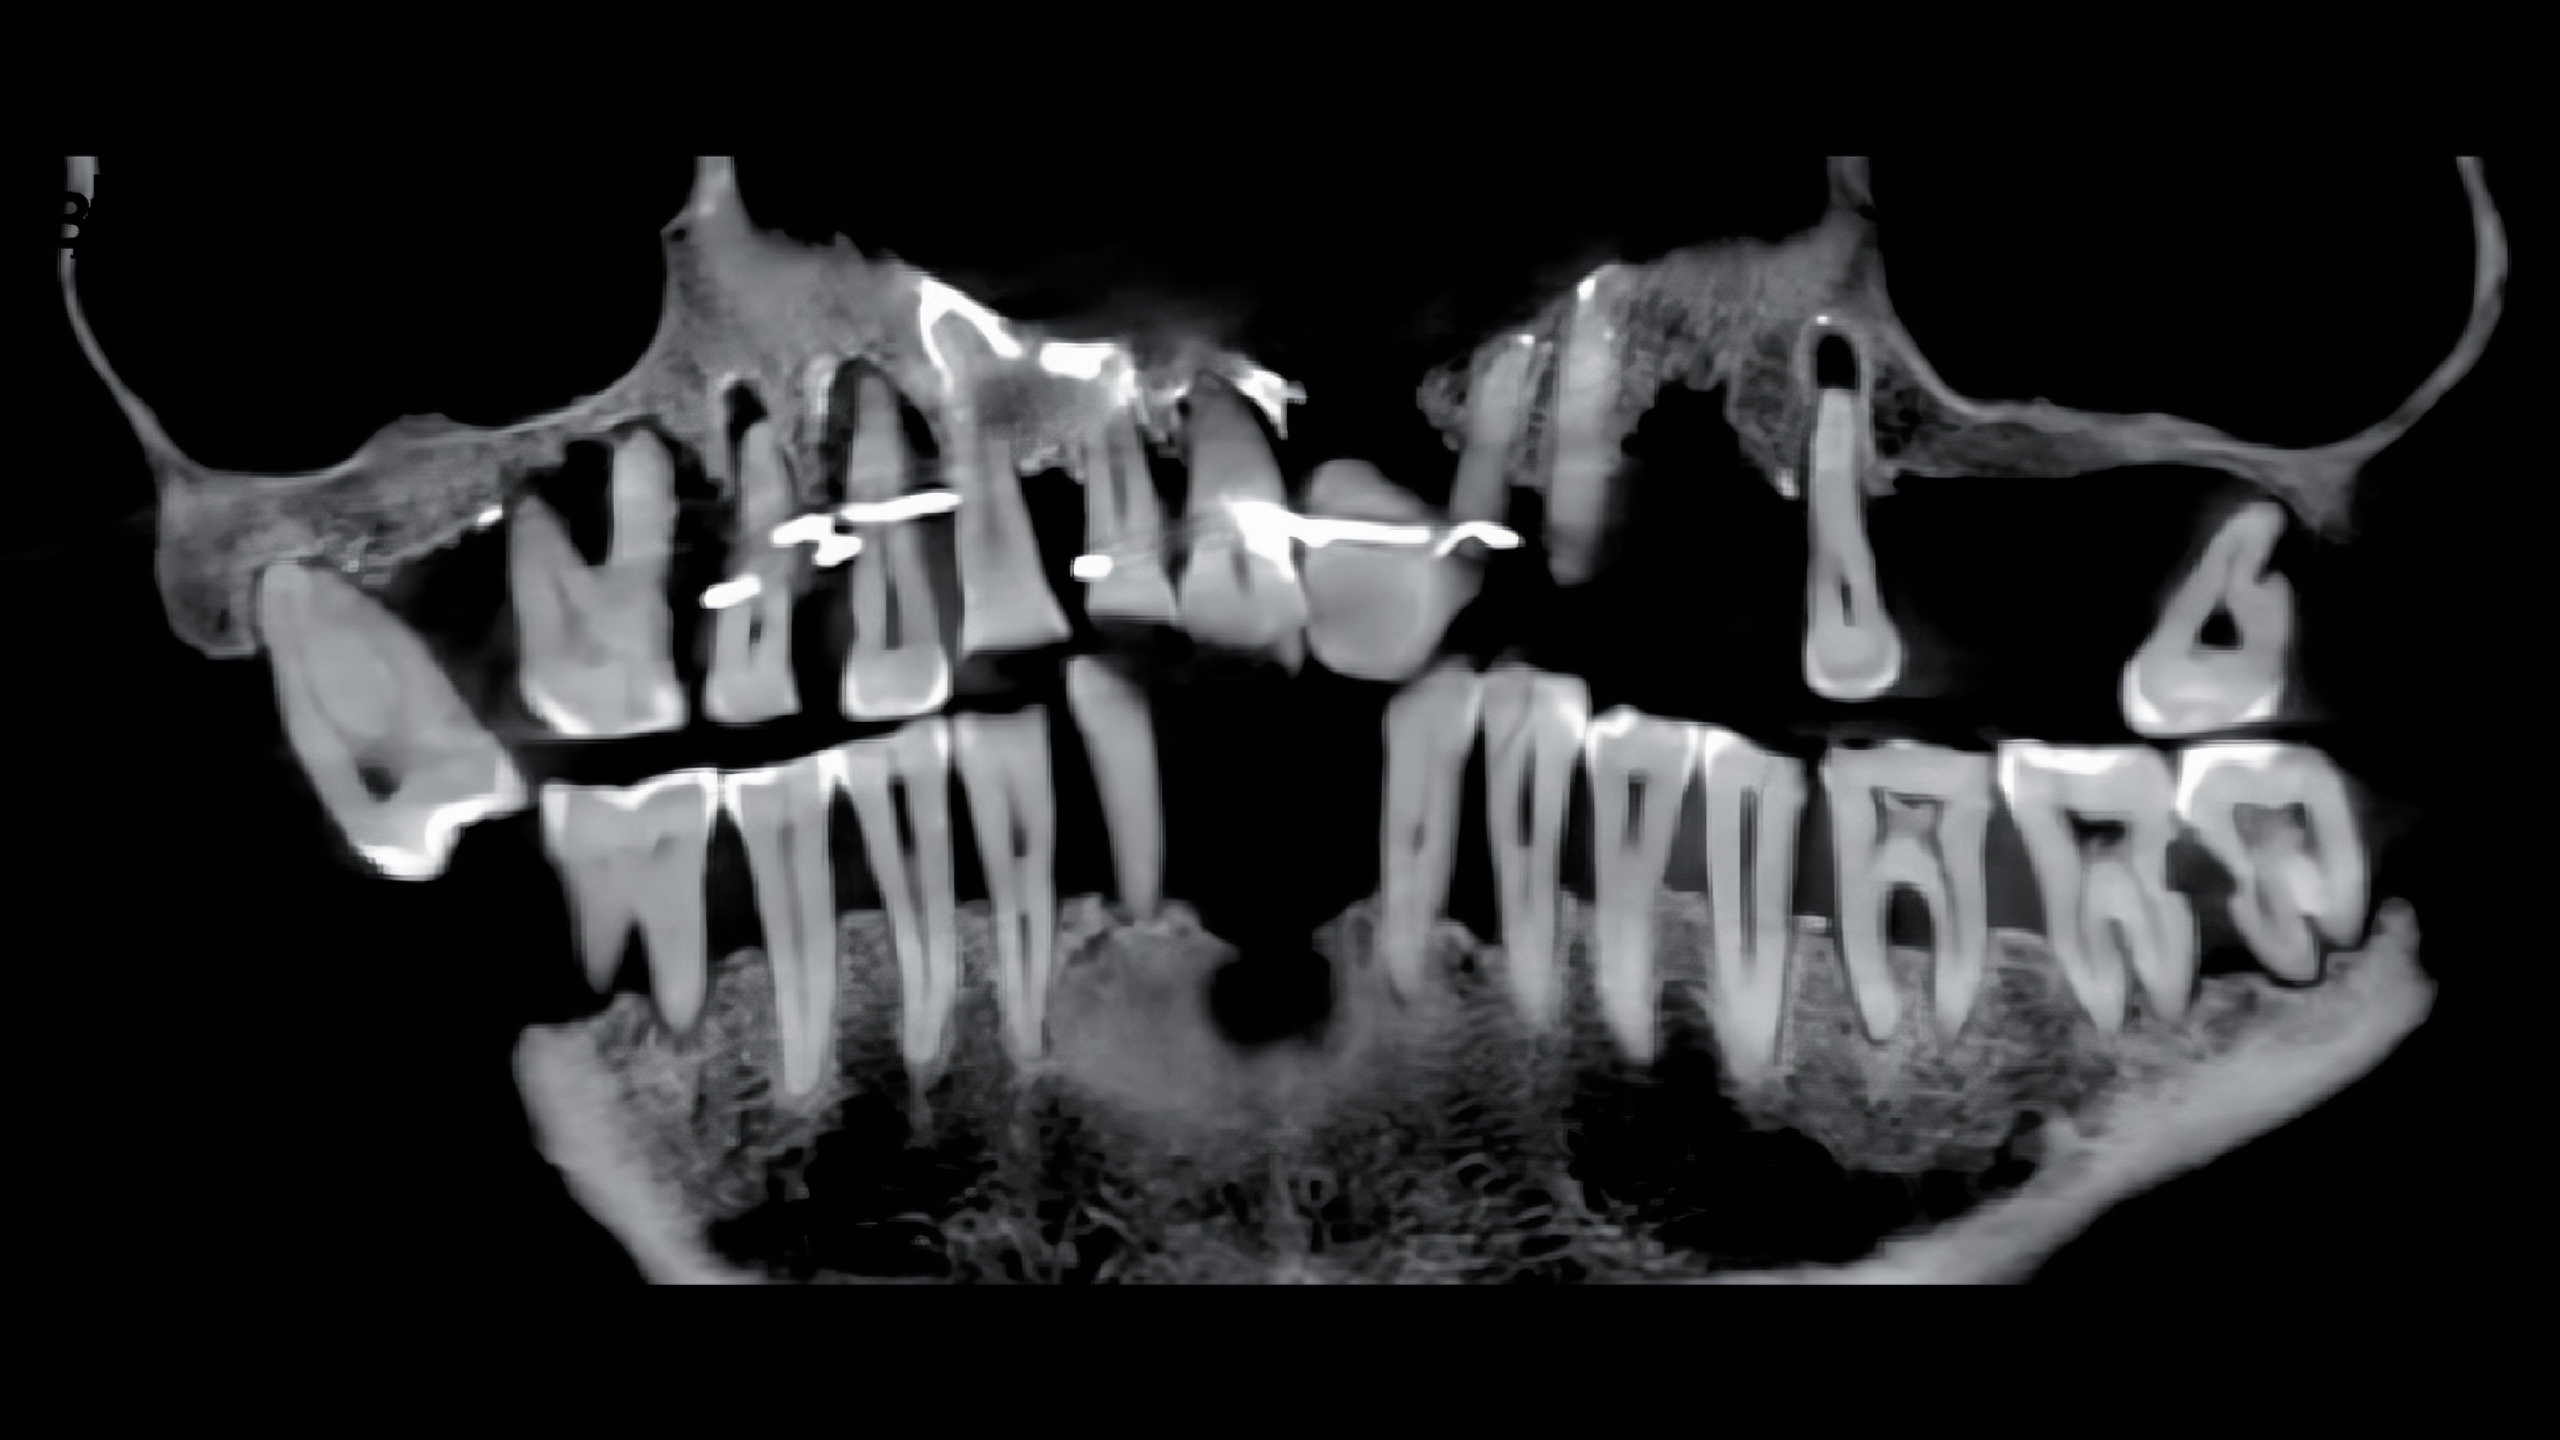

2023년 1월 24일 Journal of Archaeological Science: Reports에 공간된 연구성과에서 X선을 사용하여 3차원 이미지를 만드는 "콘 빔cone beam"으로 그의 두개골을 스캔한 결과 d'Alègre는 심각한 치주 질환periodontal disease을 앓았으며

이때문에 많은 치아가 느슨해졌고 그런 치아가 빠지지 않도록 미세한 금 와이어fine gold wires를 삽입했다는 사실이 밝혀냈다.

이 와이어는 잇몸 근처 치아 바닥을 감았다. 치아 중 일부는 와이어를 넣고자 뚫린 상태였고, 이미 이빨 일부가 빠져 그 부분은 코끼리 상아로 만든 가짜 치아도 넣었다. 임플란트? 시술 비슷하게 한 셈이다.

이런 치아 고정 방식이 지금은 원시적이겠지만 당시에는 혁신적인 치료법이었다고 한다.

하지만 이런 치료는 고통스러웠을 것이고, 와이어를 주기적으로 다시 조여야 했을 것이라고 한다.

이런 잦은 치료가 주변 치아까지 더 불안하게 만들었을 것이라고 한다.